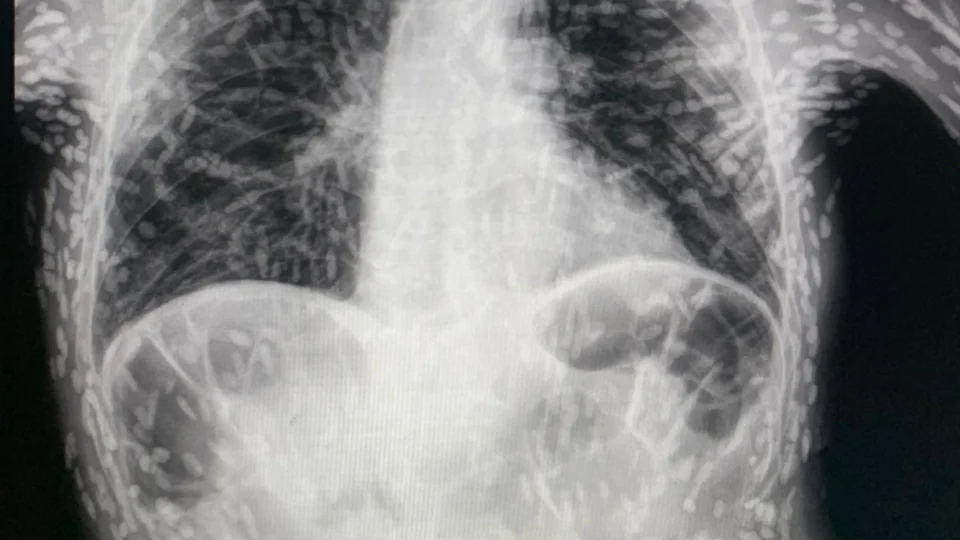

O médico Vitor Borin de Souza compartilhou a radiografia do tórax de um paciente com doença parasitária, cheio de ovos de verme, no último domingo (16), em São Paulo.

No exame de imagem é possível ver os ovos de tênia pelo corpo do paciente, diagnosticado com um quadro de cisticercose.

Conforme o médico, residente pelo Hospital das Clínicas de Botucatu (SP), a doença é adquirida a partir da ingestão do ovo da tênia.

O médico acrescenta que a doença não é ocasionada por carne mal cozida e sim, por vegetais contaminados, sem lavagem.

Vitor Borin sinalizou aos internautas, preocupados com o estado do paciente, que os ovos de tênia encontrados já estavam mortos.

O médico informou que, não identificada lesão na cabeça, medula e olhos, não há necessidade de tratamento.

Vitor Borin explicou que os vermes calcificados estão inviáveis, inativos.

No caso do paciente do raio-x, o médico comunicou que o paciente solicitou o exame após apresentar 2 meses de tosse.